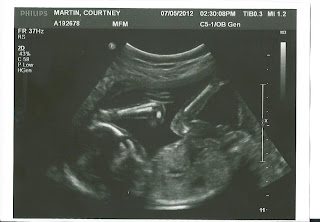

Ultrasound @ 19 weeks

Baby weighs 11oz

Sure has changed alot from that tiny blob from the first ultrasound at only 8 weeks. He was very wiggly when she was looking at him. Cannot believe the detail when we got to watch him move on the big screen. It was too cool! She said his foot was like the size of your 1st joint of your pinky finger.

Here we go: